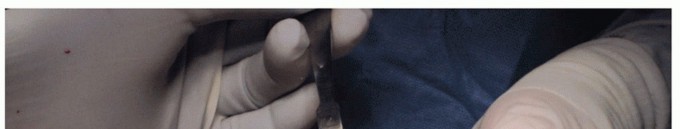

Drill Hole and Placement of Taper Post Screw

Tap the drill hole to the etched line (TECH FIG 2A-C).

Place the tapered screw of the HemiCAP DF implant, gaining purchase within the distal metatarsal bone. Bring the line indicator on the screwdriver just flush with the depth of the remaining articular surface level (TECH FIG 2D,E).

- TECH FIG 2 • A. A tap is used within the first metatarsal head, stopping at the etched line on the driver when flush with the plantar articular surface. B. A taper post screw is placed to the etched line when flush with the joint surface. C. Intraoperative use of tap to etched line using inferior aspect as reference point. D. Intraoperative screw placement. E. The screw is stopped when the etched line is flush with the remaining joint surface using the inferior aspect as the reference point. F. Screw can be advanced past etched line if bony decompression desired. Each one quarter-turn past the line equals 1 mm additional joint decompression. (continued)